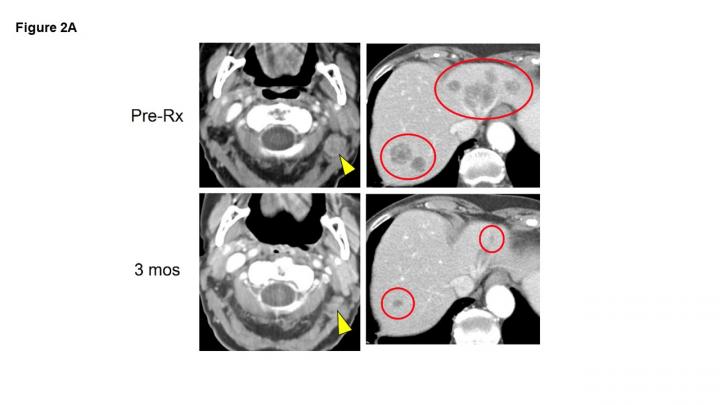

In the 50-patient study of pembrolizumab as the initial treatment for patients with recurrent, locally advanced or metastatic Merkel cell carcinoma, more than half of the patients (28 patients, 56 percent) had long-lasting responses to the treatment, 12 of whom (24 percent) experienced a complete disappearance of their tumors. Nearly 70 percent of patients in this study were alive two years after starting treatment.

Patients in the just-published study received the immune checkpoint blocking drug pembrolizumab intravenously every three weeks for up to two years. During this time, the status of their cancer was monitored periodically with imaging scans. Overall, most patients tolerated the treatment well. However, 28 percent of patients experienced serious side effects, including one treatment-associated death.